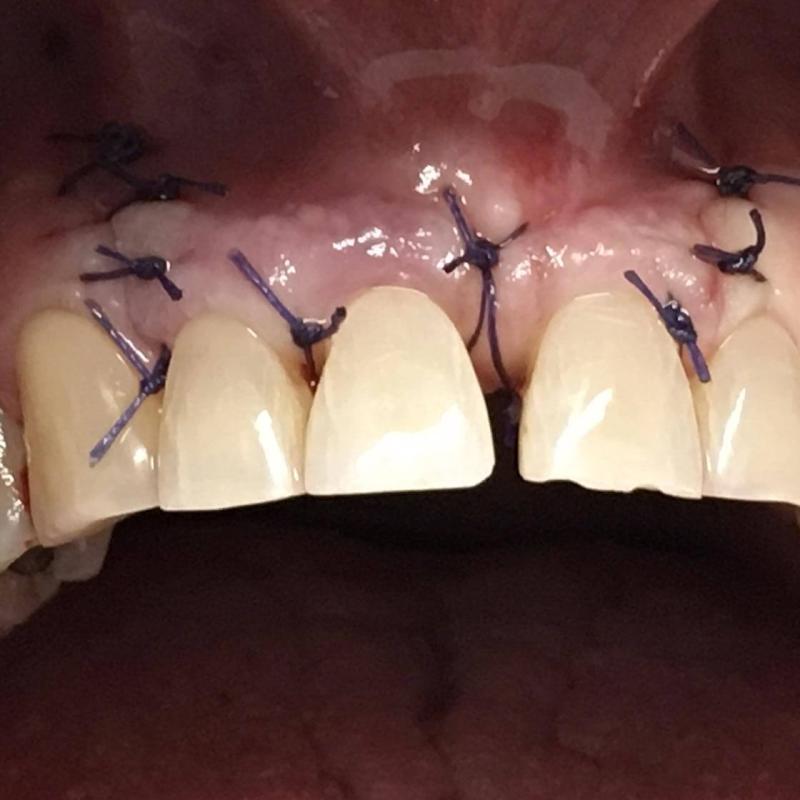

La parodontologia controlla il benessere delle strutture portanti dei denti (gengive e osso di sostegno) cercando di prevenire o curare la piorrea che nella popolazione adulta è la più frequente causa di perdita dei denti.

Oggi più che mai viene richiesta la copertura di esposizioni radicolari mediante la chirurgia estetica mucogengivale. Inoltre con la cura della piorrea si mantiene in buono stato la salute generale del paziente prevenendo complicanze cardiovascolari e diabetiche.